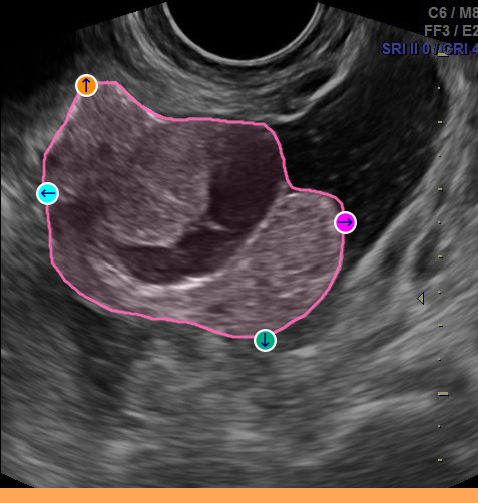

However, in the medical domain, overlapping structures, blurred boundaries, and heuristically defined contours undermine the specificity of point prompts, forcing annotators to rely on more descriptive prompts such as bounding boxes or numerous refinement points. In practice, point prompts trap users in a greedy correction loop: an initial click yields an imprecise mask, which is refined iteratively with new points, each patching local errors instead of working toward a coherent description of the instance as a whole (Fig. 2(a)). Worse, additional refinements can introduce new errors, as the instance identity is gradually established rather than defined upfront. Bounding boxes address identity more directly, but they only constrain the region of interest, leaving the model to infer boundaries with little guidance. They are also cognitively inefficient to draw, as annotators must rely on mental imagery to locate the object’s extremities and position box corners that are not visually anchored, which slows annotation [papadopoulos2017extreme].

A natural alternative is to mark these extremities directly. The extreme points method [papadopoulos2017extreme] asks annotators to click the top-, bottom-, left-, and right-most points of an instance (Fig. 2ii). This bypasses the need to manually place box corners, as they can be computed automatically, while also providing richer information through four boundary points anchored on the object itself. In their daily practice, clinicians rely on a related but distinct convention: to measure structures in ultrasound, they mark the endpoints of the major and minor axes, a simple gesture that encodes geometry, orientation, and extent (Fig. 2iii). We refer to these as the major/minor points. Both 4-points strategies are fast, intuitive, and better capture instance identity, yet SAM-like models have not been adapted to exploit them.

Across eight datasets in ultrasound and surgical endoscopy, S4M achieves consistent gains of +3.42 mIoU over a strong specialist SAM baseline at equal prompt budget (Fig. 2iv). Importantly, it does so while reducing the cognitive load of annotation: by replacing iterative error-finding and correction with more informative 4-point prompts upfront, S4M makes the process faster and less demanding. As it modifies only the prompt encoding stage, the approach remains fully compatible with standard box, region-based, refinement prompts, and adaptable to other SAM-based designs. Finally, an annotation study with three clinicians demonstrates that major/minor point prompts can be collected efficiently, confirming the practical benefit of the proposed approach.